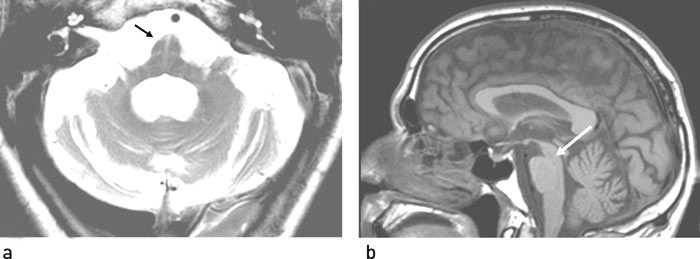

Diagnosen hviler først og fremst på den kliniske vurderingen, men av og til kan supplerende undersøkelser gi diagnostisk hjelp. Autonome tester med måling av blodtrykk og puls liggende kan avdekke autonom svikt (12). MR-undersøkelse av hjernen kan i noen tilfeller avdekke forandringer som er karakteristiske for tilstanden. I 60 % av tilfellene kan man finne en periputaminal hyperintensitet, som er nesten patognomonisk (13). Det kan videre avsløres atrofi av putamen, nedre del av hjernestammen, hjernepedunkler og cerebellum, og også høysignal i hjernestammen (cross bun sign) (fig 2a). I klinisk praksis er det likevel som oftest forløpet av sykdommen og den manglende klare responsen på levodopa som etter hvert sannsynliggjør diagnosen.

Diagnostisk er det typiske kliniske bilde med tidlig falltendens og reduserte vertikale øyebevegelser viktigste måte å skille progressiv supranukleær parese fra Parkinsons sykdom. MR-undersøkelse av hjernen kan i mer avanserte tilfeller vise tydelig atrofi av mesencephalon med utseende som en fugl i sideplan (hummingbird (kolibri) sign) (fig 2b).